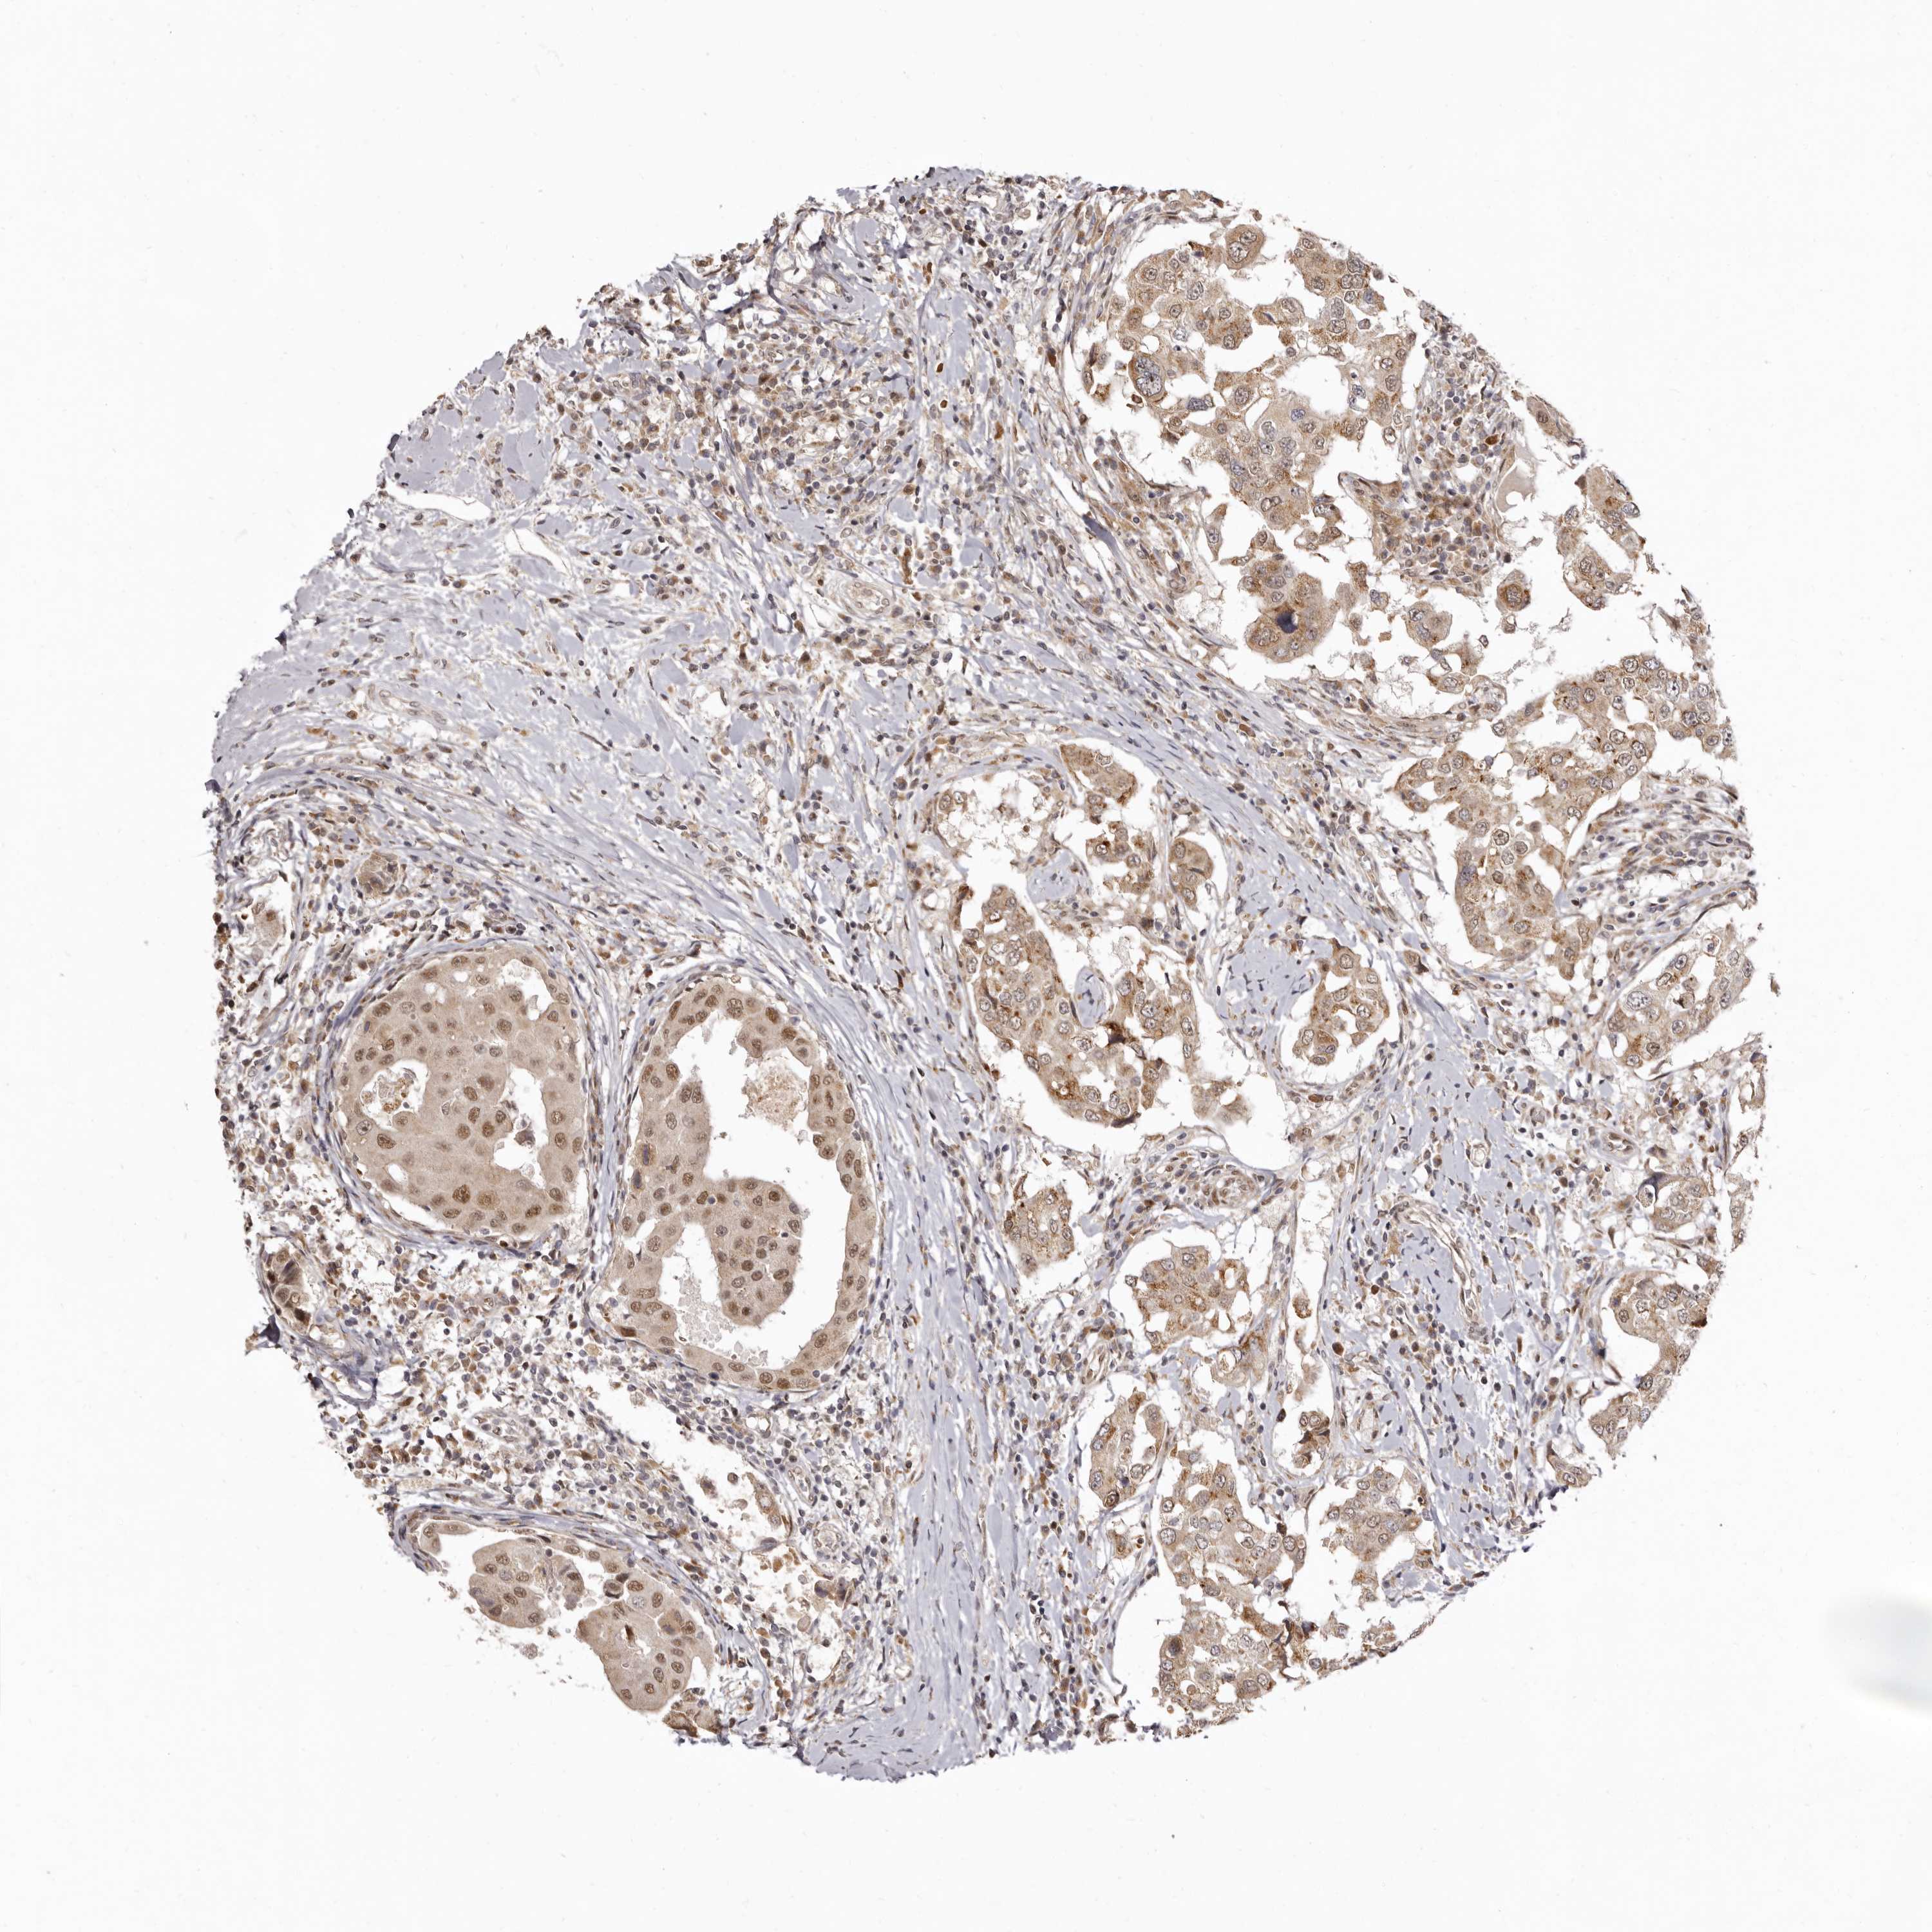

BRCA TCGA BRCA VALIDATION PROTEIN EXPRESSION